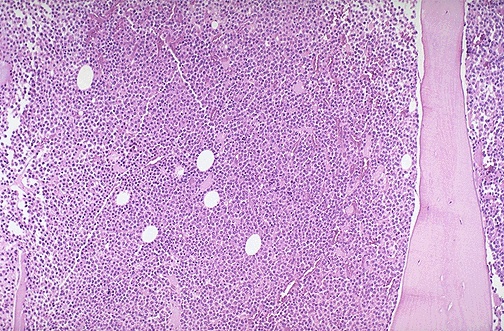

At low power, the abnormal plasma cells of multiple myeloma fill the marrow.